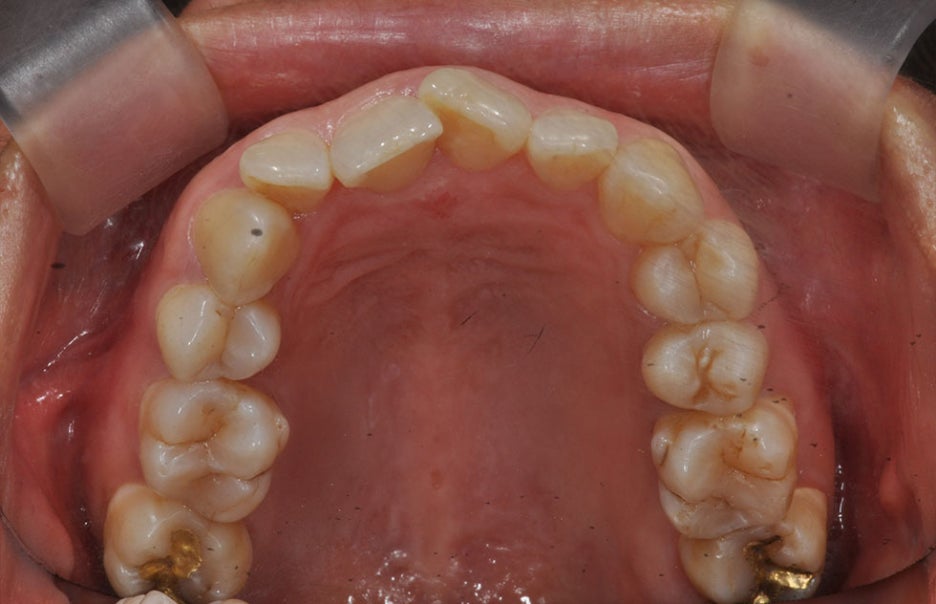

치아교정이 필요한 경우는?

치아 교정은 기능적으로 올바른 교합관계가

필요한 경우, 편안하게 구강위생을 관리하는

목적으로 시행할 수 있습니다. 심미적으로는

외모를 보완하고 심리적인 흡족함을

가져다줄 수 있습니다.

서울교정잘하는치과 저희 뉴엔은 치아와

치아 사이에 틈이 큰 벌어진 치아의 경우,

치아가 고르지 못하며 비뚤어진 경우,

교합이 일정하지 않은 엇갈린 치아,

아랫니와 윗니가 다물어지지 않는 교합인

경우로 다물지 못하는 치아일 때, 윗니가

아랫니를 과하게 덮은 교합인 경우,

반대로 아랫니가 윗니를 덮어 정상 교합에서

반대되는 교합인 경우 등에

교정치료를 적용하고 있습니다.